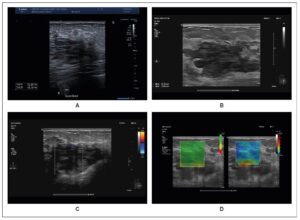

Initial ultrasonography revealed a heterogeneous 3.5 × 2 cm mass, and cytology suggested a benign hemorrhagic–inflammatory lesion (Figure 1). After a course of antibiotics, follow-up MRI demonstrated a well-demarcated 6 × 4 × 4.5 cm mass with T2 hyperintensity and diffusion, features compatible with an abscess (Figure 2). The lesion also showed progressive, atypical contrast enhancement, prompting further sampling. Microbiopsies revealed benign granulation tissue undergoing fibro-hyaline organization with telangiectatic vascular clefts (Nottingham Class B2).

Three months later, the lesion had increased in size. Ultrasound was used as the initial imaging modality due to its accessibility. It demonstrated a multilobulated, poorly defined 5 × 4 × 2 cm mass, heterogeneous, compressible, and non-indurated on elastography, with no detectable vascularization on color Doppler (Figure 1). Fine-needle aspiration—performed first due to the hemorrhagic risk associated with suspected vascularity—yielded only blood, and cytology remained nondiagnostic (C1 Nottingham). A vascular tumor was therefore considered.